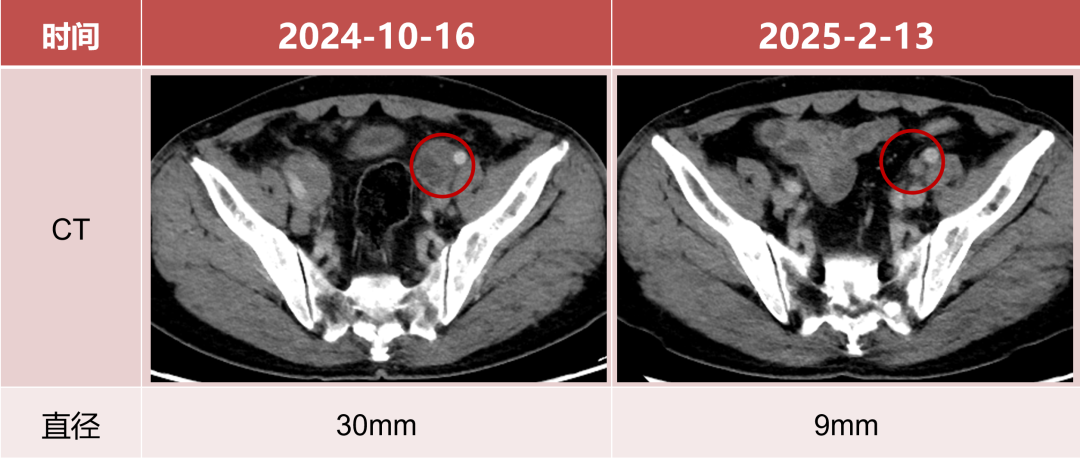

用药16周后淋巴结评估

• 左髂血管旁淋巴结直径较前减小70%。

图片9.png

• 左锁骨下淋巴结直径较前减小53.8%。

图片10.png